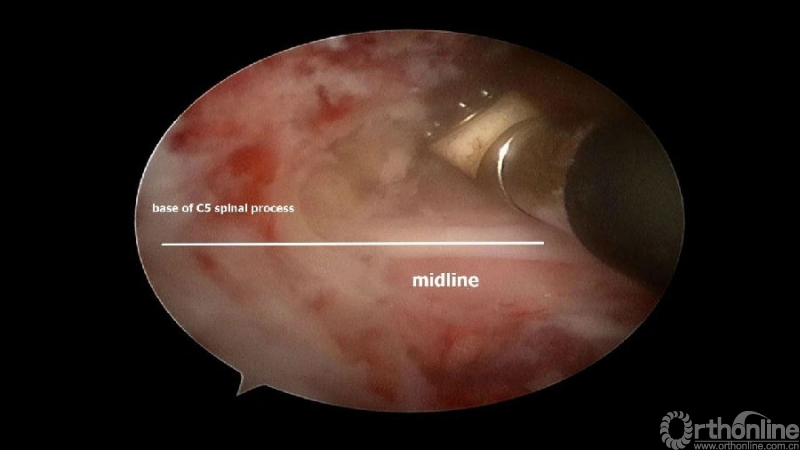

颈椎内镜下单侧入路双侧减压(ULBD)中,减压的难点还是在于识别棘突与椎板的移行部位及对侧结构的显露。

临床上,0°镜子绝对是颈椎UBE的最好用的镜子,但是30°的镜子对侧中线结构的显露及对侧结构的显露具有更广角的视野。在进行同侧减压之前,中线结构的显露是关键。

1. 术中如何确定中线?